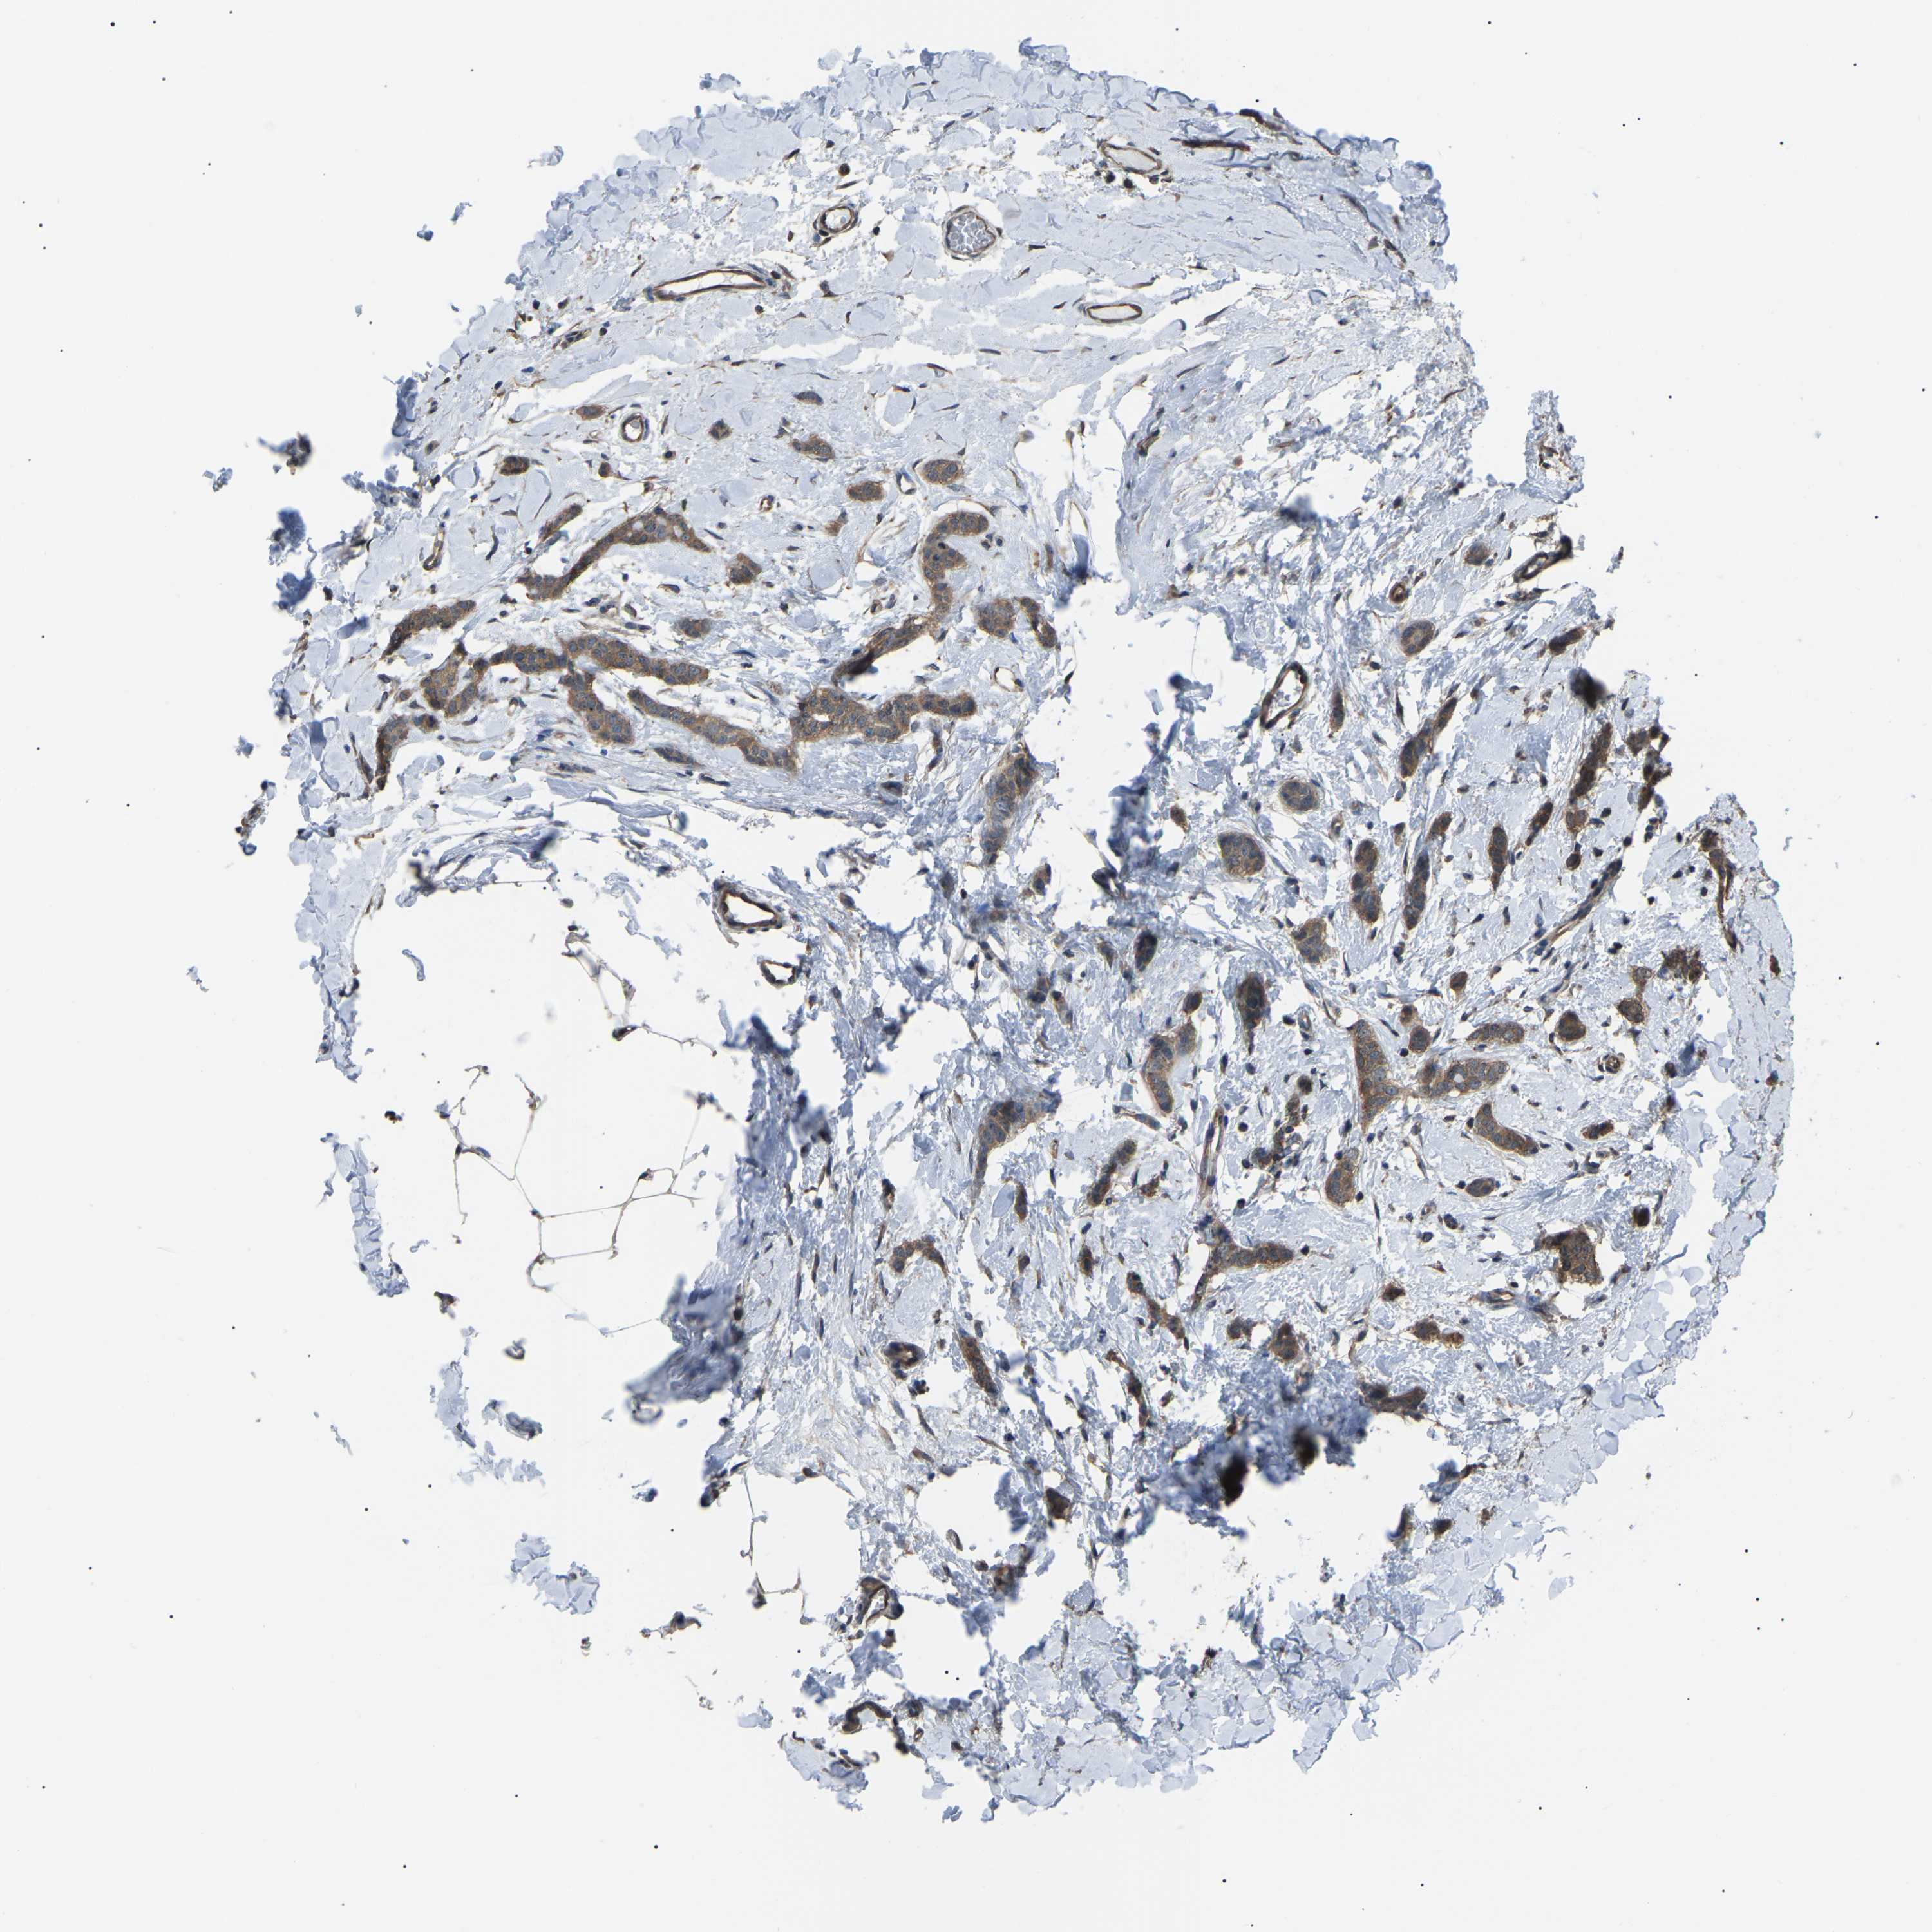

CANCER BREAST CANCER Show tissue menu

BRCA TCGA BRCA VALIDATION PROTEIN EXPRESSION

Breast cancer

Human cancer